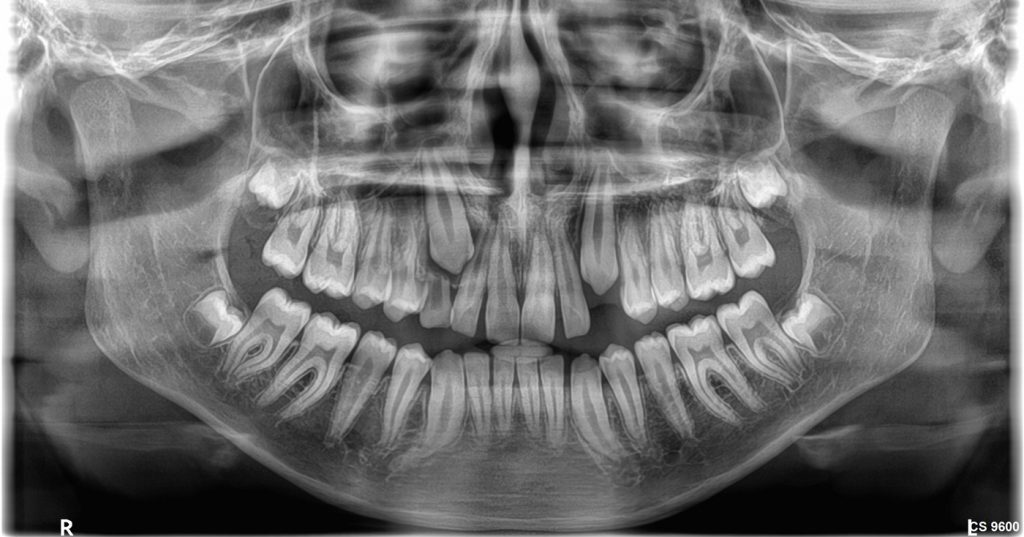

- Άριστη ψηφιακή Πανοραμική ακτινογραφία (2D).